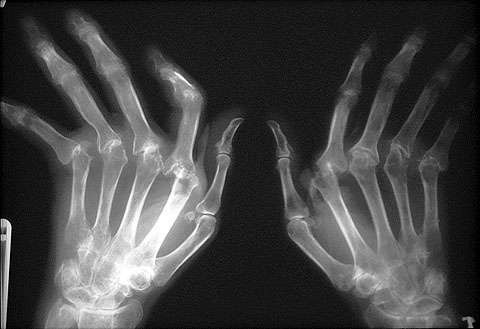

Inflammatory Arthritide: - Symmetrical distribution - Bilateral uniform loss of joint space - Rat Bite erosions - Pannus formation - Localized periarticular osteoporosis - DIP’s spared - Atlanto-axial instability - Haygarth’s Nodes @ MCP (knuckle) - Swan Neck / Boutonniere deformity - Ulnar/Fibular deviation (Lanois) of fingers/toes

Rheumatoid Arthritis (RA)